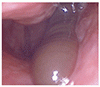

ハナビル

Nasal Leech

それまで健康であった男性が,10 日前から片側の鼻孔から血が滴り落ちると訴えて来院した.20 日前に山の湧き水で顔を洗ったという.鼻腔内視鏡でヒルが見つかった(動画で示す).